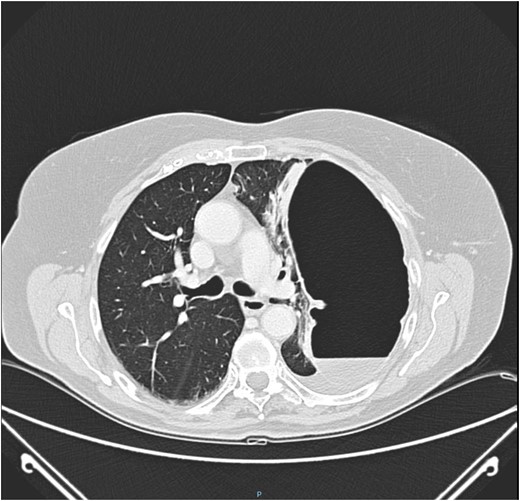

Thoraco-abdominal computed tomography (CT) showed the herniated bowel (transverse colon), translocated through a defect of about 7 cm in the left hemidiaphragm (Figs 2–4), a rightward deviation of the mediastinal structures and an atelectasis of the left lung (Fig. 5). The left colon had the appearance of a volvulus.

CT of chest showing defect on left side of the diaphragm and colon herniation in the thoracic cavity.